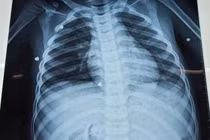

Được biết, bệnh nhân nhập viện trong tình trạng khó thở dữ dội, phù toàn thân, vô niệu, tụt huyết áp, rối loạn ý thức. Kết quả thăm dò cho thấy hẹp van động mạch chủ nặng, suy tim EF 30%, rung nhĩ, suy gan – thận, giảm tiểu cầu, rối loạn đông máu, toan chuyển hóa và viêm phổi.

Nữ bệnh nhân đã tỉnh táo, hô hấp và tuần hoàn ổn định.

Sau 7 ngày điều trị tích cực với nhiều kỹ thuật chuyên sâu, tình trạng người bệnh dần cải thiện, các chỉ số xét nghiệm trở về ngưỡng an toàn. Bệnh nhân tỉnh táo, hô hấp và tuần hoàn ổn định.